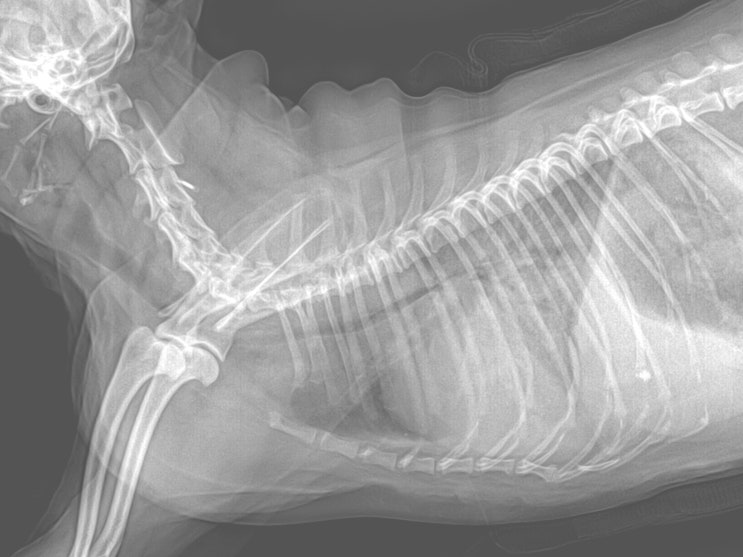

15살 말티즈 강아지 간종양 수술 없이 관리 후기 / 반려견 간종양 꼭 수술해야 하나요? / 댕댕이 간이 큰 이유, 원인 / 노령견 간암 증상, 치료, 관리법

안녕하세요~ 굿파파 수의사입니다. 벌써 점심시간이 지났네요 행복한 미소 가득한 하루 보내세요 오늘의 포...